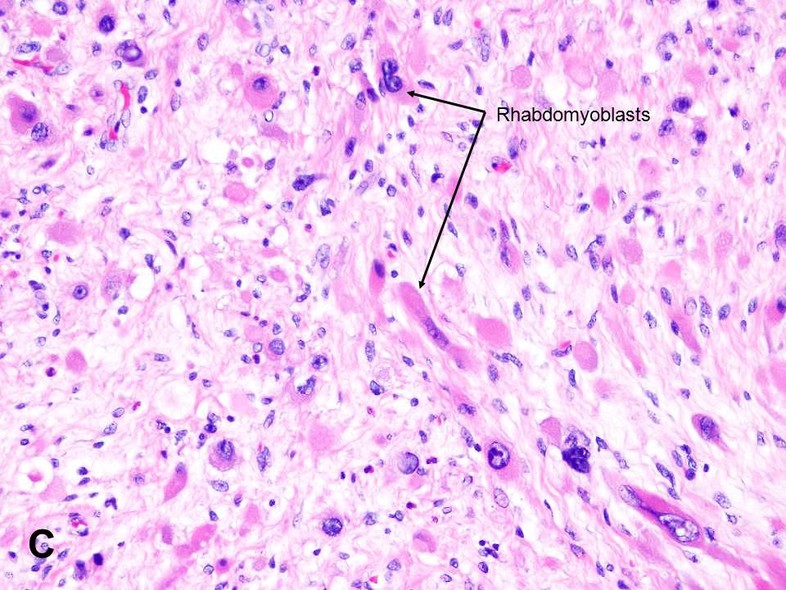

Pleomorphic Rhabdomyosarcoma | Basicmedical Key

basicmedicalkey.com

basicmedicalkey.com

rhabdomyosarcoma pleomorphic